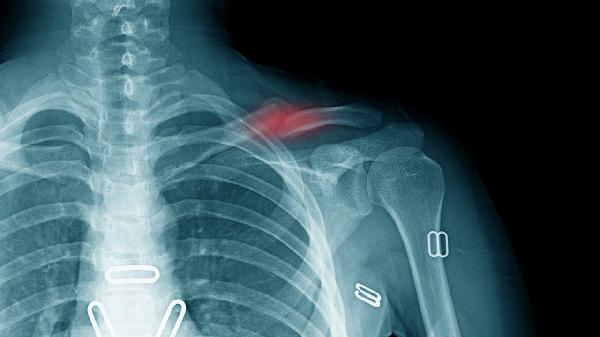

冠状动脉供血不足时可能出现心前区压榨性疼痛,可向左肩背部放射,多由劳累或情绪激动诱发。需立即舌下含服硝酸甘油片,并遵医嘱长期服用阿司匹林肠溶片、单硝酸异山梨酯缓释片等。建议完善心电图、冠脉CTA等检查,避免剧烈运动和寒冷刺激。